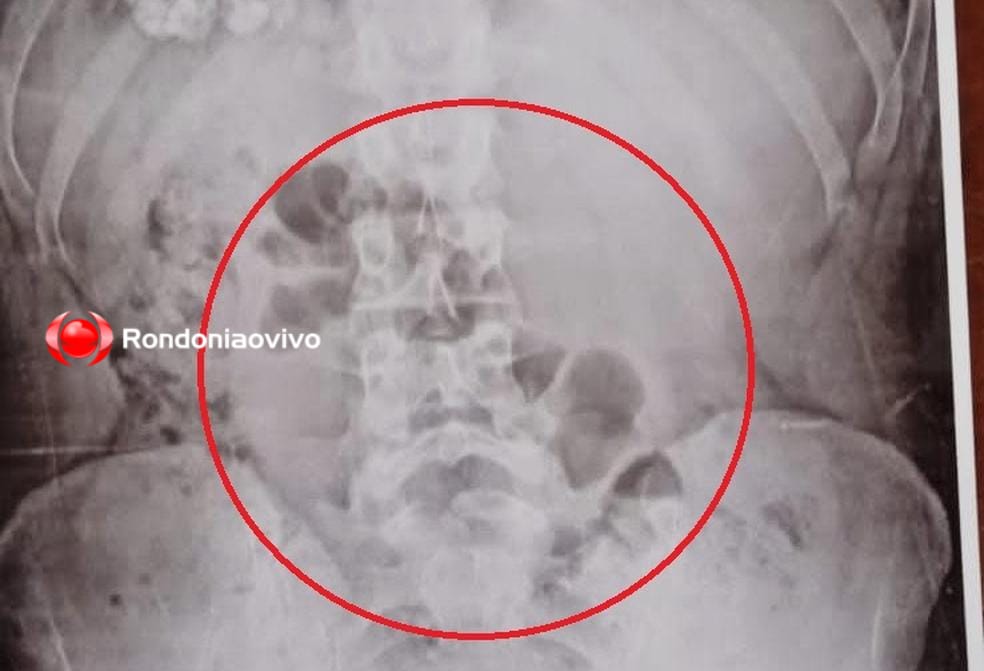

Mulher foi descoberta com a droga no estômago durante revista através do equipamento de raio-X

A mulher foi descoberta com a droga no estômago durante revista através do equipamento de raio-X.